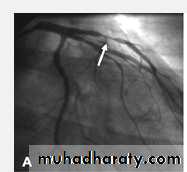

Severe proximal LAD Lesion

CVS

Very severe proximal LAD stenosis

Total CX Occlusion